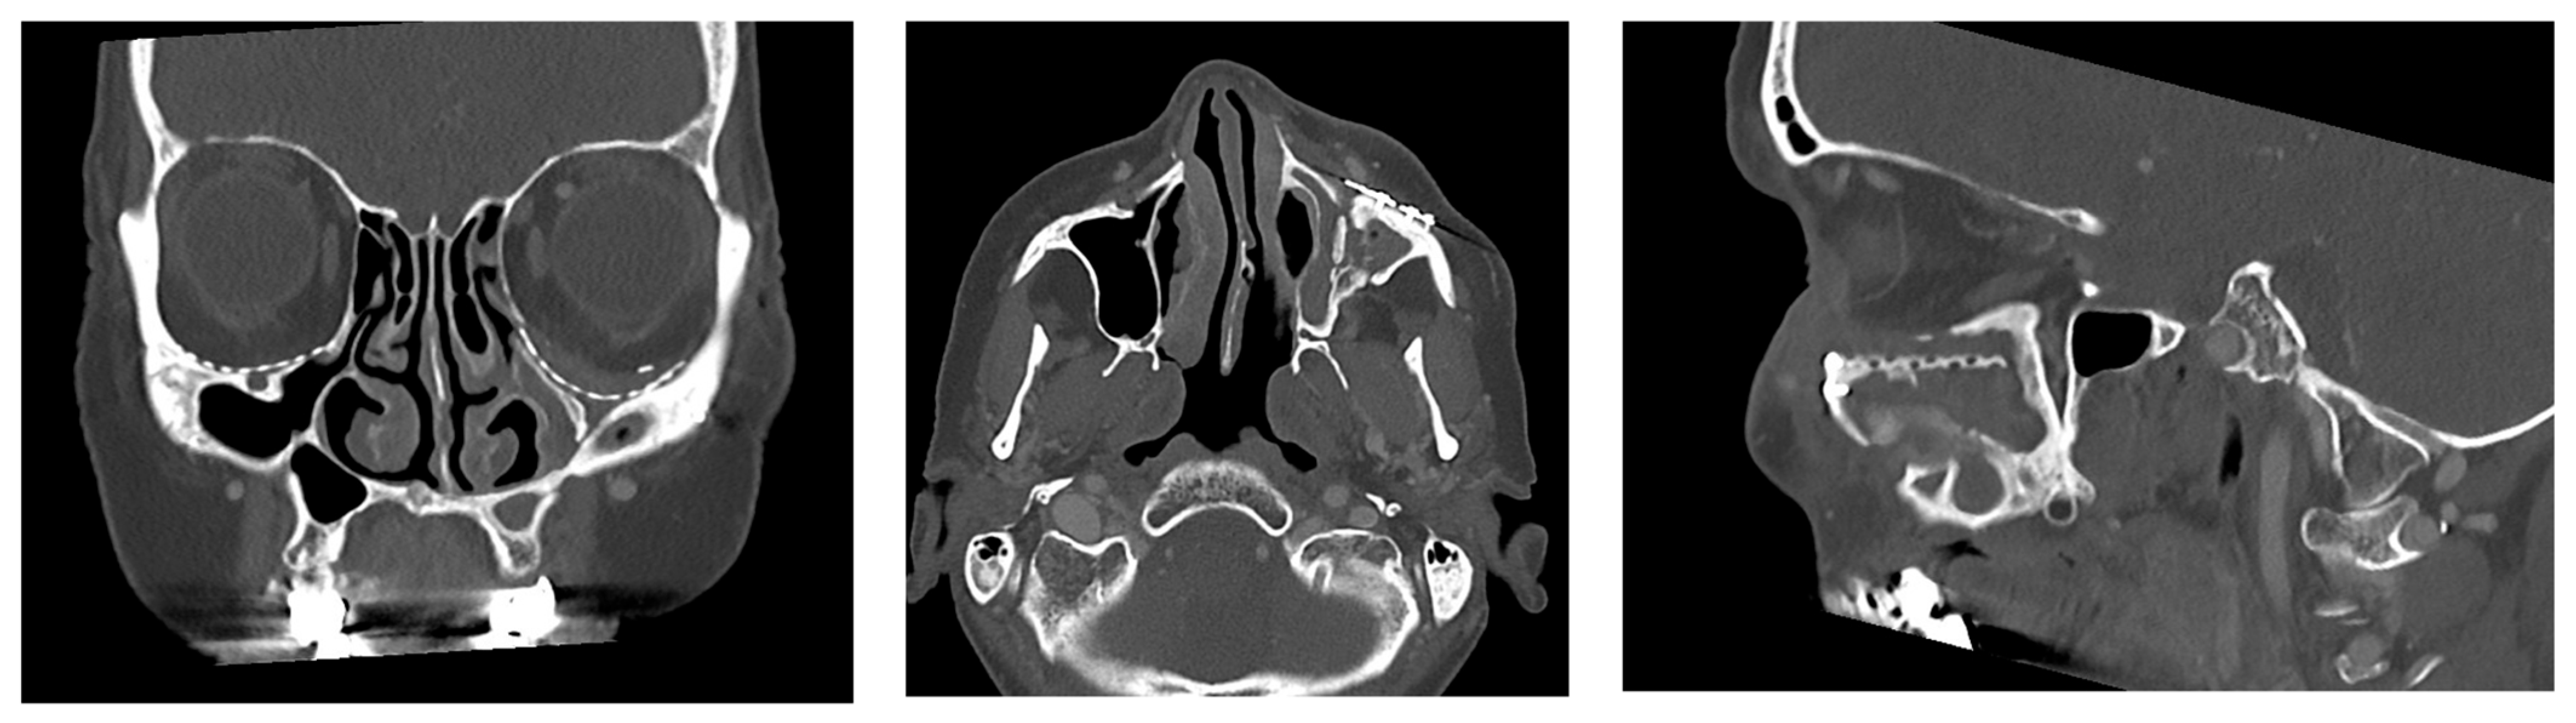

- Patent ostium of the maxillary sinus (coronal plane)

- Non-inflammatory PNSs (three planes)

- Exposure of the osteosynthesis screws (axial and sagittal planes)

- Exposure of the PSI to the maxillary sinus (coronal and sagittal planes)

- Remodeling of the fractured orbital walls and bone apposition at the PSI indicating osseointegration (three planes)